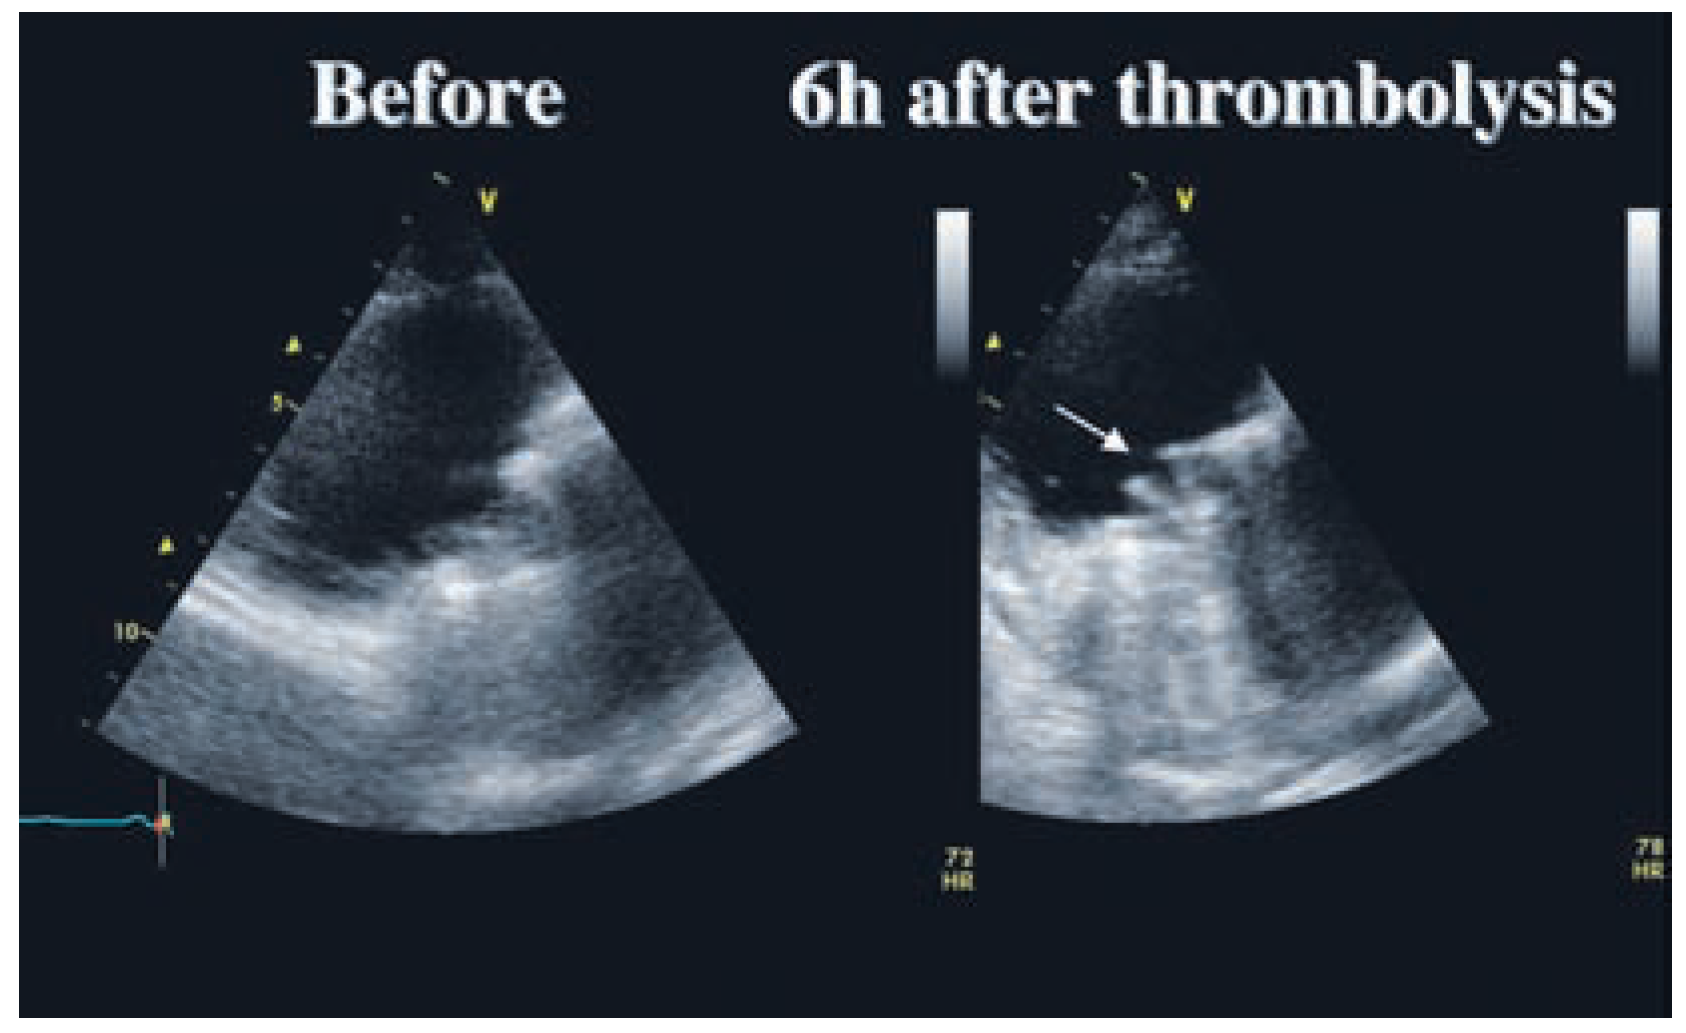

Thrombolysis of a Tricuspid Prosthetic Valve

Case report